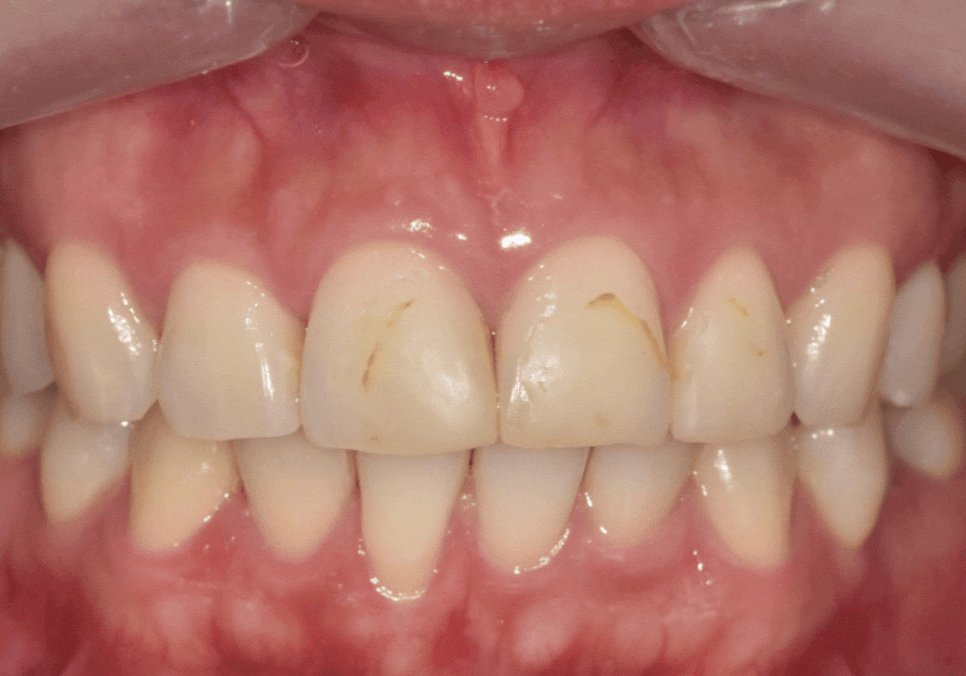

그런데 1년 정도 지나고 나니

레진을 붙였던 부위가

갈색으로 비쳐 보이기 시작했다고 하셨어요.

250726

먼저 방사선 사진으로 확인해보니

다행히 2차 충치가 뚜렷하게 보이거나,

문제가 있어 보이지 않았습니다.

이럴 때는

새로 레진을 하기 보다는

눈에 띄는 겉면만

폴리싱(연마, 다듬기)으로 정리해도

변색된 부분을 충분히 지울 수가 있습니다.